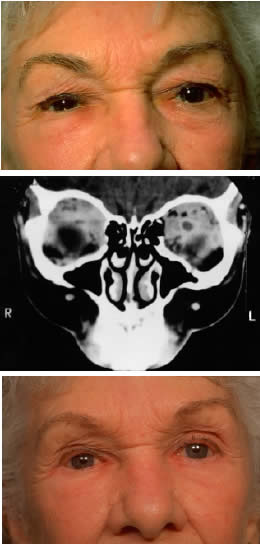

Fig. 4. A 36-year-old white woman presented with a 3-month history of progressive left proptosis associated with a retrobulbar pressure sensation. On external examination, she had bossing of the temporalis fossa and a proptosis of 9 mm axially, with a slight downward displacement of the globe. Ocular ductions were full, and there was no evidence of optic nerve compromise. CT scan on axial (A) and coronal (B) views confirmed a hyperostosing sphenoid wing meningioma with soft tissue components in the posterolateral orbit and anterior middle cranial fossa. During the next 20 months, her proptosis progressed to 11 mm, accompanied by increasing headaches and ocular pain, ocular restriction, and blurred vision in abduction. She underwent tumor resection with a combined frontotemporal orbitozygomatic approach, and she remains without evidence of recurrence 5 years after surgery. Visual function was preserved, and proptosis decreased to 2 mm.

Fig. 5. A 48-year-old Chinese woman had undergone previous frontotemporal craniotomy and partial excision of a left sphenoid wing meningioma. She presented 6 years later with progressive proptosis, visual loss, and numbness of the left cheek and upper teeth that developed during the preceding 2 years. On external examination, she had fullness of the temporalis fossa, an axial proptosis of 11 mm, and downward displacement of the left globe 2 mm (A). Ocular ductions were moderately restricted in all fields of gaze. She had no light perception, marked optic disc pallor, and an optociliary shunt vessel. CT scan revealed an extensive regrowth of meningioma involving the sphenoid wing, with soft tissue components in the temporalis and middle cranial fossae, parasellar region, and orbit, shown here on axial view (B). The lesion also involved the cavernous sinus and pterygopalatine fossa. She underwent a combined resection via the frontotemporal orbitozygomatic approach, followed by radiotherapy (50 Gy in 25 fractions over 5 weeks) for residual components in the cavernous and sphenoid sinuses. Two years after surgery, she remains comfortable and without radiographic evidence of tumor regrowth. Proptosis was reduced to 1 mm axially.